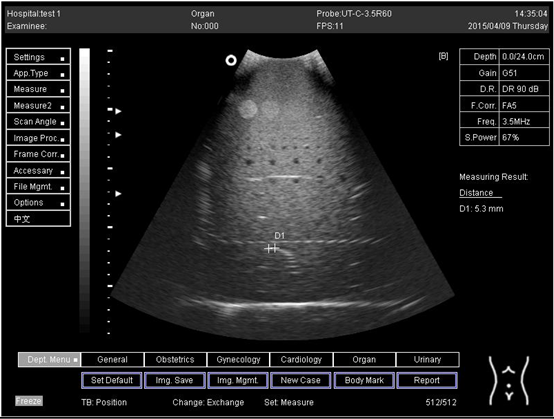

16.0Axial resolution

Biomimetics 07 00130 i025

D1 = 5.6

D2 = 4.1

D3 = 3.0

Lateral resolution

Biomimetics 07 00130 i026

D1 = 5.0